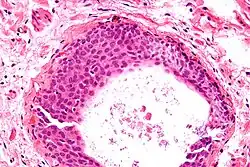

- Uniform nuclei with irregular borders and nuclear grooves (insert image).

They appear as white/yellow cysts or nodules that can reach a size of 2 millimeters. They typically have elliptical nuclei with a long groove (along the major axis) – so-called "coffee bean" nuclei.

It has been suggested that these cell rests are the histogenetic origins of Brenner tumors, due to the histological similarity of the epithelium of Walthard cell rests and Brenner tumors to the urothelium of the lower urinary tract. Also, it has been proposed that Brenner tumors and Walthard cell rests signify urothelial differentiation within the female genital tract.

High magnification micrograph of a Brenner tumor showing the characteristic coffee bean nuclei which are also seen in Walthard cell rests. H&E stain.